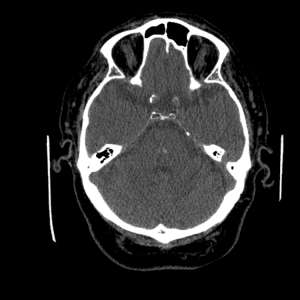

Non-traumatic Head CT Cases

Classic Cases

Includes classic examples of cases commonly seen on call.